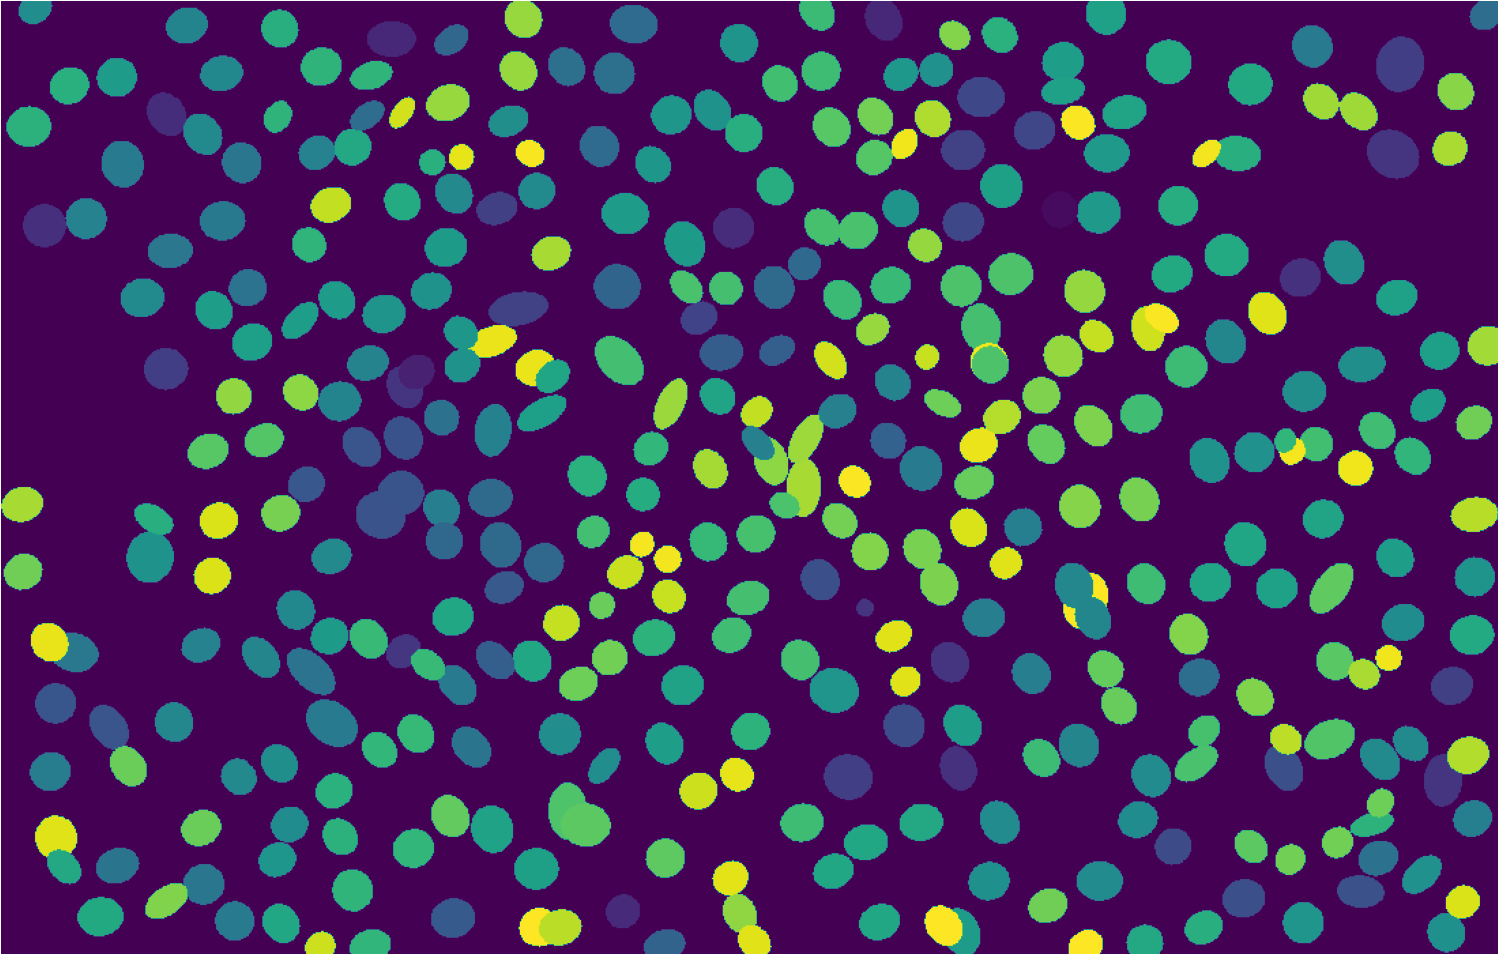

We evaluated the proposed method on three publicly available cell microscopy datasets provided from the ISBI 2015 Cell Tracking Challenge [39]: Fluo-N2DH-GOWT1, PhC-C2DH-U373, and Fluo-N2DL-HeLa, illustrated in Fig. 6. Each dataset contains two sequences in the training set (with ground truth annotations) and two challenge sequences (without ground truth annotation), named with suffices -01 and -02. The results for the challenge sequences are obtained by submitting the results to the ISBI challenge server. We proceed to provide details regarding each of the chosen datasets.

Fluo-N2DH-GOWT1 contains GFP-transfected GOWT1 mouse embryonic stem cells captured on fluorescence microscopy. Challenges with this dataset include low contrast of some cells and few cells entering and exiting the imaged region from the axial direction. The capture time step is .

PhC-C2DH-U373 contains glioblastoma-astrocytoma U373 cells captured under phase contrast microscopy. This dataset is challenging due to cells having highly deformable shapes and parts of cell bodies having a similar appearance to the background. The capture time step is .

Fluo-N2DH-HeLa contains fluorescently labeled HeLa nuclei captured on fluorescence microscopy. Challenges with this dataset include high cell density, low contrast, a few irregularly shaped cells, various mitoses events, and cells entering and exiting the imaged region. The capture time step is .